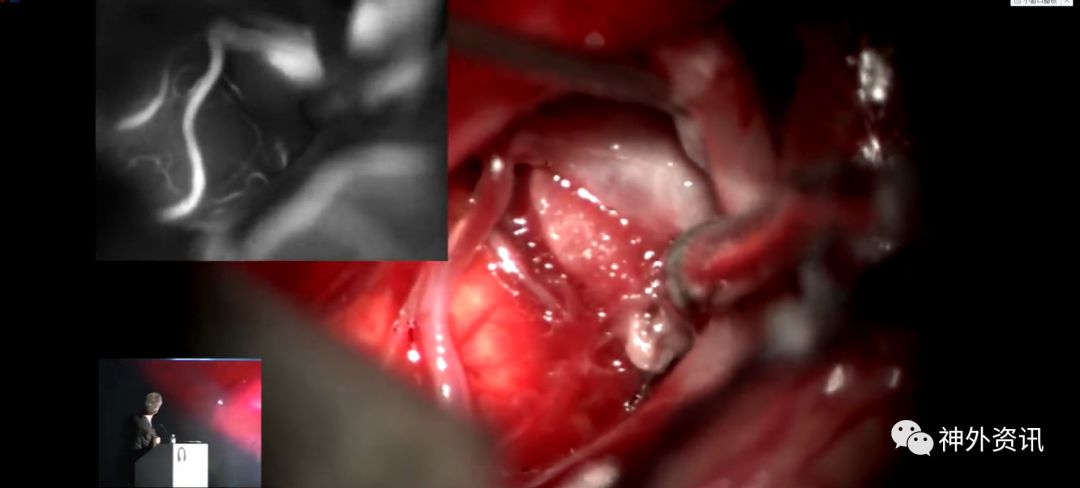

Michael T. Lawton,巴洛神经科学研究所(BNI)主席,精于各种脑血管疾病的治疗,已累及外科治疗4400余例颅内动脉瘤和700余例AVM,发表论文270余篇,参编书籍40余部,著有《Seven Aneurysms: Tenets and Techniques for Clipping》。